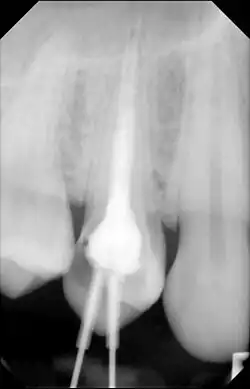

| Cone beam CT scan presenting a diffuse hyperdense lesion in the apex of a mandibular molar (arrowhead, top) adjacent to an inflammatory periapical lesion (arrow, bottom).[1] | |

Diagnosis typically involves a clinical examination by a dentist or endodontist, complemented by imaging studies such as cone-beam computed tomography. Radiographically, condensing osteitis presents as a localized radiopaque lesion at the root apex of the affected tooth.[5]